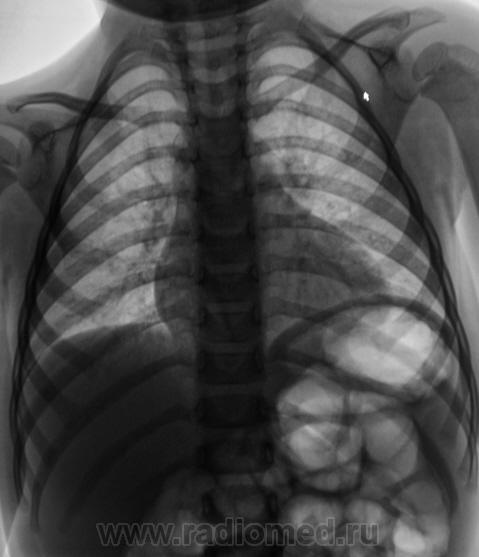

Пол пациента: Женский пол Тип патологии: Воспалительное заболевание неинфекционной природы Область исследования: Грудная клетка и верхние дыхательные пути Методы исследования: Rg Пациентка из детского отделения направлена на рентгенографию органов грудной полости с диагнозом - "Пневмония". Ваше мнение уважаемые коллеги? https://radiomed.ru/sites/default/files/styles/case_slider_image/public/user/12/2.Rebyonok.jpg?itok=dMaaWYGH ID:1367 Сб, 20/02/2010 - 22:53 #1 Анатолий Владим... Не на сайте Был на сайте: 7 лет 11 месяцев назад Зарегистрирован: 16.10.2009 - 21:16 Публикации: 1941 Пневмонической инфильтрации не видно. Вс, 21/02/2010 - 16:48 #2 Vikkur Не на сайте Был на сайте: 4 года 8 месяцев назад Зарегистрирован: 24.09.2009 - 14:34 Публикации: 1749 Не могу исглючить бронхообструктивного синдрома. Виктор. Втр, 23/02/2010 - 09:59 #3 Николай Не на сайте Был на сайте: 2 года 10 месяцев назад Зарегистрирован: 29.05.2009 - 04:38 Публикации: 554 Рентгенологических признаков пневмонии нет, легочная ткань без изменений. О бронхобструкции также речи нет. Пнд, 28/03/2011 - 08:02 #4 гана Не на сайте Был на сайте: 4 года 1 месяц назад Зарегистрирован: 12.01.2011 - 09:43 Публикации: 84 какая то рахитеческая грудная клетка,да и рисунок легочной выражен в прикорневой зоне больше слева, а сердечко - не увеличены левые границы? УЗИ сердца делали? - может врожденная патология?петли кишечника пневматизированы.

Пневмонической инфильтрации не видно.

Не могу исглючить бронхообструктивного синдрома.

Рентгенологических признаков пневмонии нет, легочная ткань без изменений. О бронхобструкции также речи нет.

какая то рахитеческая грудная клетка,да и рисунок легочной выражен в прикорневой зоне больше слева, а сердечко - не увеличены левые границы? УЗИ сердца делали? - может врожденная патология?петли кишечника пневматизированы.